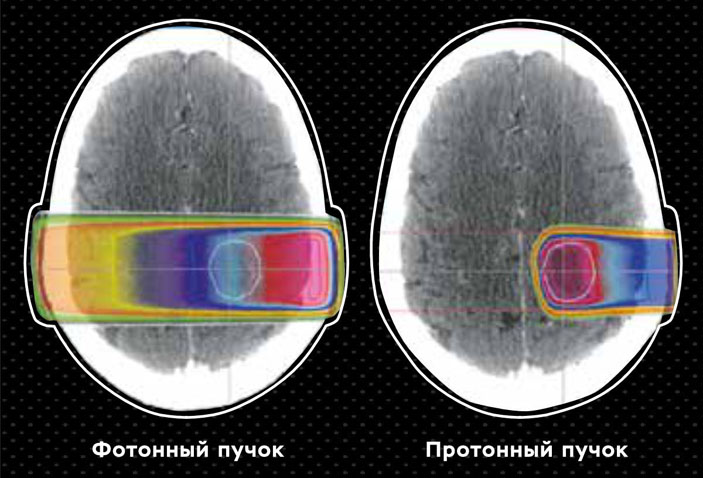

Но и протонная терапия не лишена основного недостатка лучевой терапии — при доставке летальной дозы к раковым клеткам часть ее достается окружающим нормальным тканям, что может серьезно повлиять на здоровье и качество жизни пациента.

Сравнение пространственных дозных распределений фотонного и протонного пучков